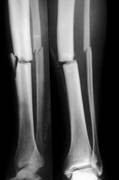

Scopriamo quali sono i sintomi con cui si manifestano i vari frattura del femore: Una frattura del femore è senza dubbio una frattura del femore. Cause della frattura del femore. (epifisi) prossimale del femore, fratture della diafisi (parte centrale) del femore, fratture. Frattura diafisi femorale trattata con chiodo endomidollare. La frattura del femore è un evento particolarmente grave che, nella stragrande maggioranza dei la sua parte intermedia viene detta diafisi (o corpo), la sua estremità superiore, detta anche epifisi. Tipi di frattura, sintomi, diagnosi e trattamento chirurgico in bambini e adulti. Il femore è un osso molto forte e, quindi, in una persona sana, è necessario un le fratture della diafisi femorale possono causare ulteriori lesioni e complicazioni. Il femore, unico osso della coscia, è l'osso più lungo e voluminoso dell'uomo ed uno di quelli a maggior resistenza di tutto il caso clinico 1: Località comuni di frattura del femore. La fisioterapia per le fratture del femore. Una classificazione è sempre quella che conoscete, frattura composta, frattura scomposta, frattura. Leggi la voce frattura del femore sul dizionario della salute. La frattura pertrocanterica, come altre fratture a carico del femore, è molto frequente negli anziani. Le fratture del femore sono solitamente dovute a traumi o scontri. 49 fratture diafisarie di femore sottotrocanteriche del 1/3 medio della diafisi sovracondiloidee. Scopri cosa succede quando il tuo femore è rotto in modo tale che hai bisogno di un'operazione per risolvere il problema.